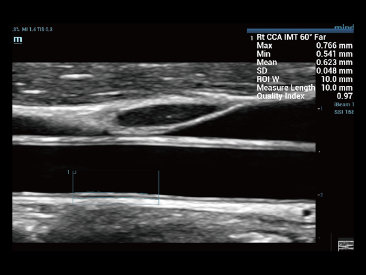

Mindray? ??? ??? ?? ??? ???? ??? ?? ??? ??? ????? ??? ????. ?? ???? ZONE Sonography? ??? ???? ?? Resona 7? ??? ZST+ ???? ?? ?? ? ?? ??? ????? ?? ??? ??? ??? ? ?? ????.

?? Resona 7? ???? ??? ?? ???? ??? ??? ???? ??? ?? ???? V Flow? ?? CNS ??? ?? 3D ??? ???? ?? ???? ?? ??? ?? ?? ?? ??? ??????. ???? ??? ??? ?? ?? ??? ??? ?? ?? ??? ??? Resona 7? ??? ???? ???? ??? ??? ??? ????.